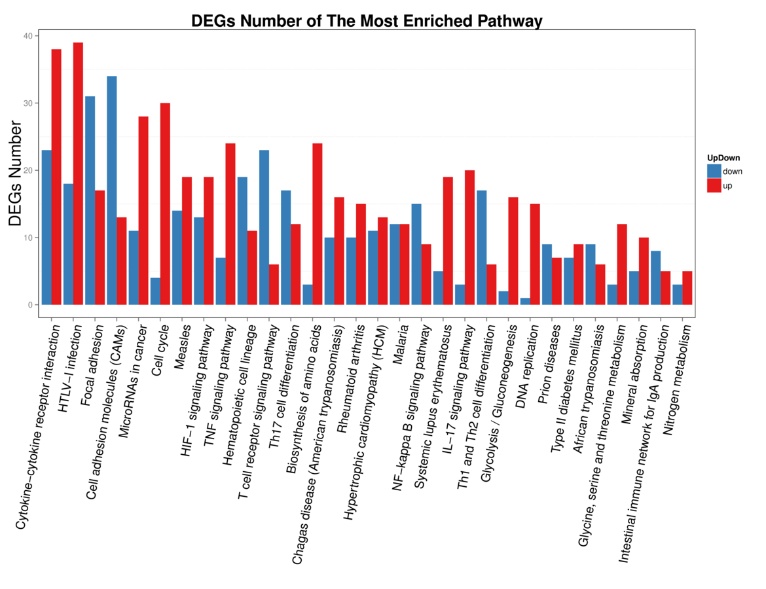

2 结果48 h各组病理结果,对照组脾组织结构正常(见图 1A )。脓毒症组脾组织见白髓结构破坏,红白髓交界模糊,多量组织细胞浸润,红髓充血(见图 1B)。差异mRNA的Volcano-plot分布图(见图 2)。相比于对照组,24 h时脓毒症组脾组织mRNA表达上调的有1 030个,下调的有935个[5];48 h组表达上调的有1 354个,下调的有1 763个。差异mRNA的聚类情况(见图 3)。GO功能分类结果(见图 4)。脓毒症大鼠脾组织部分通路相关基因表达情况(见图 5、6):脓毒症大鼠24 h,48 h脾组织关于细胞因子及其受体相互作用通路相关基因的分布图(见图 7,图 8)。脓毒症大鼠24 h,48 h脾组织关于细胞凋亡相关通路的基因分布图(见图 9,图 10)。

| X轴:GO功能分类,Y轴:对应GO Term中的基因数。 图 5 脓毒症大鼠24 h组 |

| 图 6 脓毒症大鼠48 h组 |

早期过度炎症反应、晚期免疫抑制系脓毒症的重要机制之一[6-7]。脾脏为人体免疫器官,在血源性抗原出现时,负责启动免疫反应[9]。脓毒症时SIRS反应可引起脾功能障碍[10]。本研究发现脓毒症48 h大鼠脾组织白髓结构破坏,红白髓交界模糊,其结构改变可能影响其免疫功能。既往对脓毒症大鼠24 h采用基因芯片分析发现部分基因表达异常[11]。若能进一步研究其早晚期的相关基因表达变化也许对脓毒症脾功能障碍有进一步的诠释。本研究采用RNA-seq技术对脓毒症大鼠早晚期脾组织行mRNA检测,是既往研究的深入,发现脓毒症早期组脾组织基因上下调数远少于晚期组,如脓毒症24 h组脾组织mRNA上调数1 030个,下调数935个,而48 h组mRNA上调数1 354个,下调数1 763个,差异明显(见图 2),符合疾病的发展过程。从图 3看,脓毒症24 h、48 h部分区域从红色趋于变浅甚至变蓝,浅蓝趋于蓝色,直观的反应脓毒症时脾脏基因表达量变化情况。从GO功能分类结果(图 4)得知,cellular processes、Environmental informationProcessing、Genetic Information Processing、Human Diseases、Metabolism、Organismal Systems相关功能基因随时间发展出现差异表达数为上升趋势。进而我们对其分析发现,脓毒症早晚期脾mRNA出现变化主要涉及细胞因子与其受体相互作用、IL-17、T细胞受体、TH1、TH2细胞分化、TNF、Toll受体、凋亡等相关信号通路。研究显示,脓毒症晚期免疫抑制可能是脓毒症患者死亡的主要原因,免疫治疗可能是未来一大趋势[12-15]。本文拟从炎症反应与细胞凋亡相关通路来阐述脓毒症脾功能障碍的相关机制。